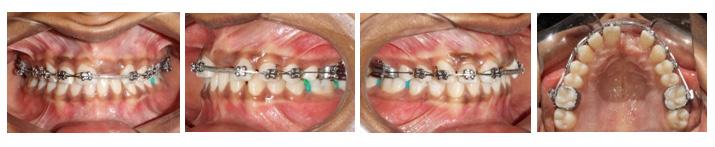

All selfies at T0 and T1 were cropped up to the clavicle of the subject if visible. The backgrounds of the selfies were removed and turned white with the help of Adobe Photoshop CC 2020 version 21.1 software package (Adobe Systems, San Jose, CA). One example of pre-treatment and post-treatment selfies of a subject in skeletal class I is illustrated in Figure 1A and 1B, in skeletal

Figure 1: Skeletal Class I Group (SCI) Male.

A-Pre-treatment (T0) Selfie; B- Post-treatment (T1) Selfie; C. Pretreatment Profile Silhouette (T0). D. Post-treatment Profile Silhouette

Figure 2: Skeletal Class II Group (SCII) Female.

A-Pre-treatment Selfie (T0), B- Post-treatment Selfie (T1). C. Pretreatment Profile Silhouette (T0), D. Post-treatment Profile Silhouette (T1).

Figure 3: Skeletal Class II Group (SCII) Female.

class II is illustrated in Figure 2A and 2B, and in skeletal class III is illustrated in Figures 3A and 3B.

All profile photographs at T0 and T1 were cropped up to the clavicle of the subject. Profile photographs were converted into black silhouettes against a white background using Adobe Photoshop CC 2020 version 21.1 software package (Adobe Systems, San Jose, CA) One example of pre-treatment and posttreatment profile silhouettes of a subject in skeletal class I is illustrated in Figure 1C and 1D, in skeletal class II is illustrated in Figure 2C and 2D, and in skeletal class III is illustrated in Figure 3C and 3D.